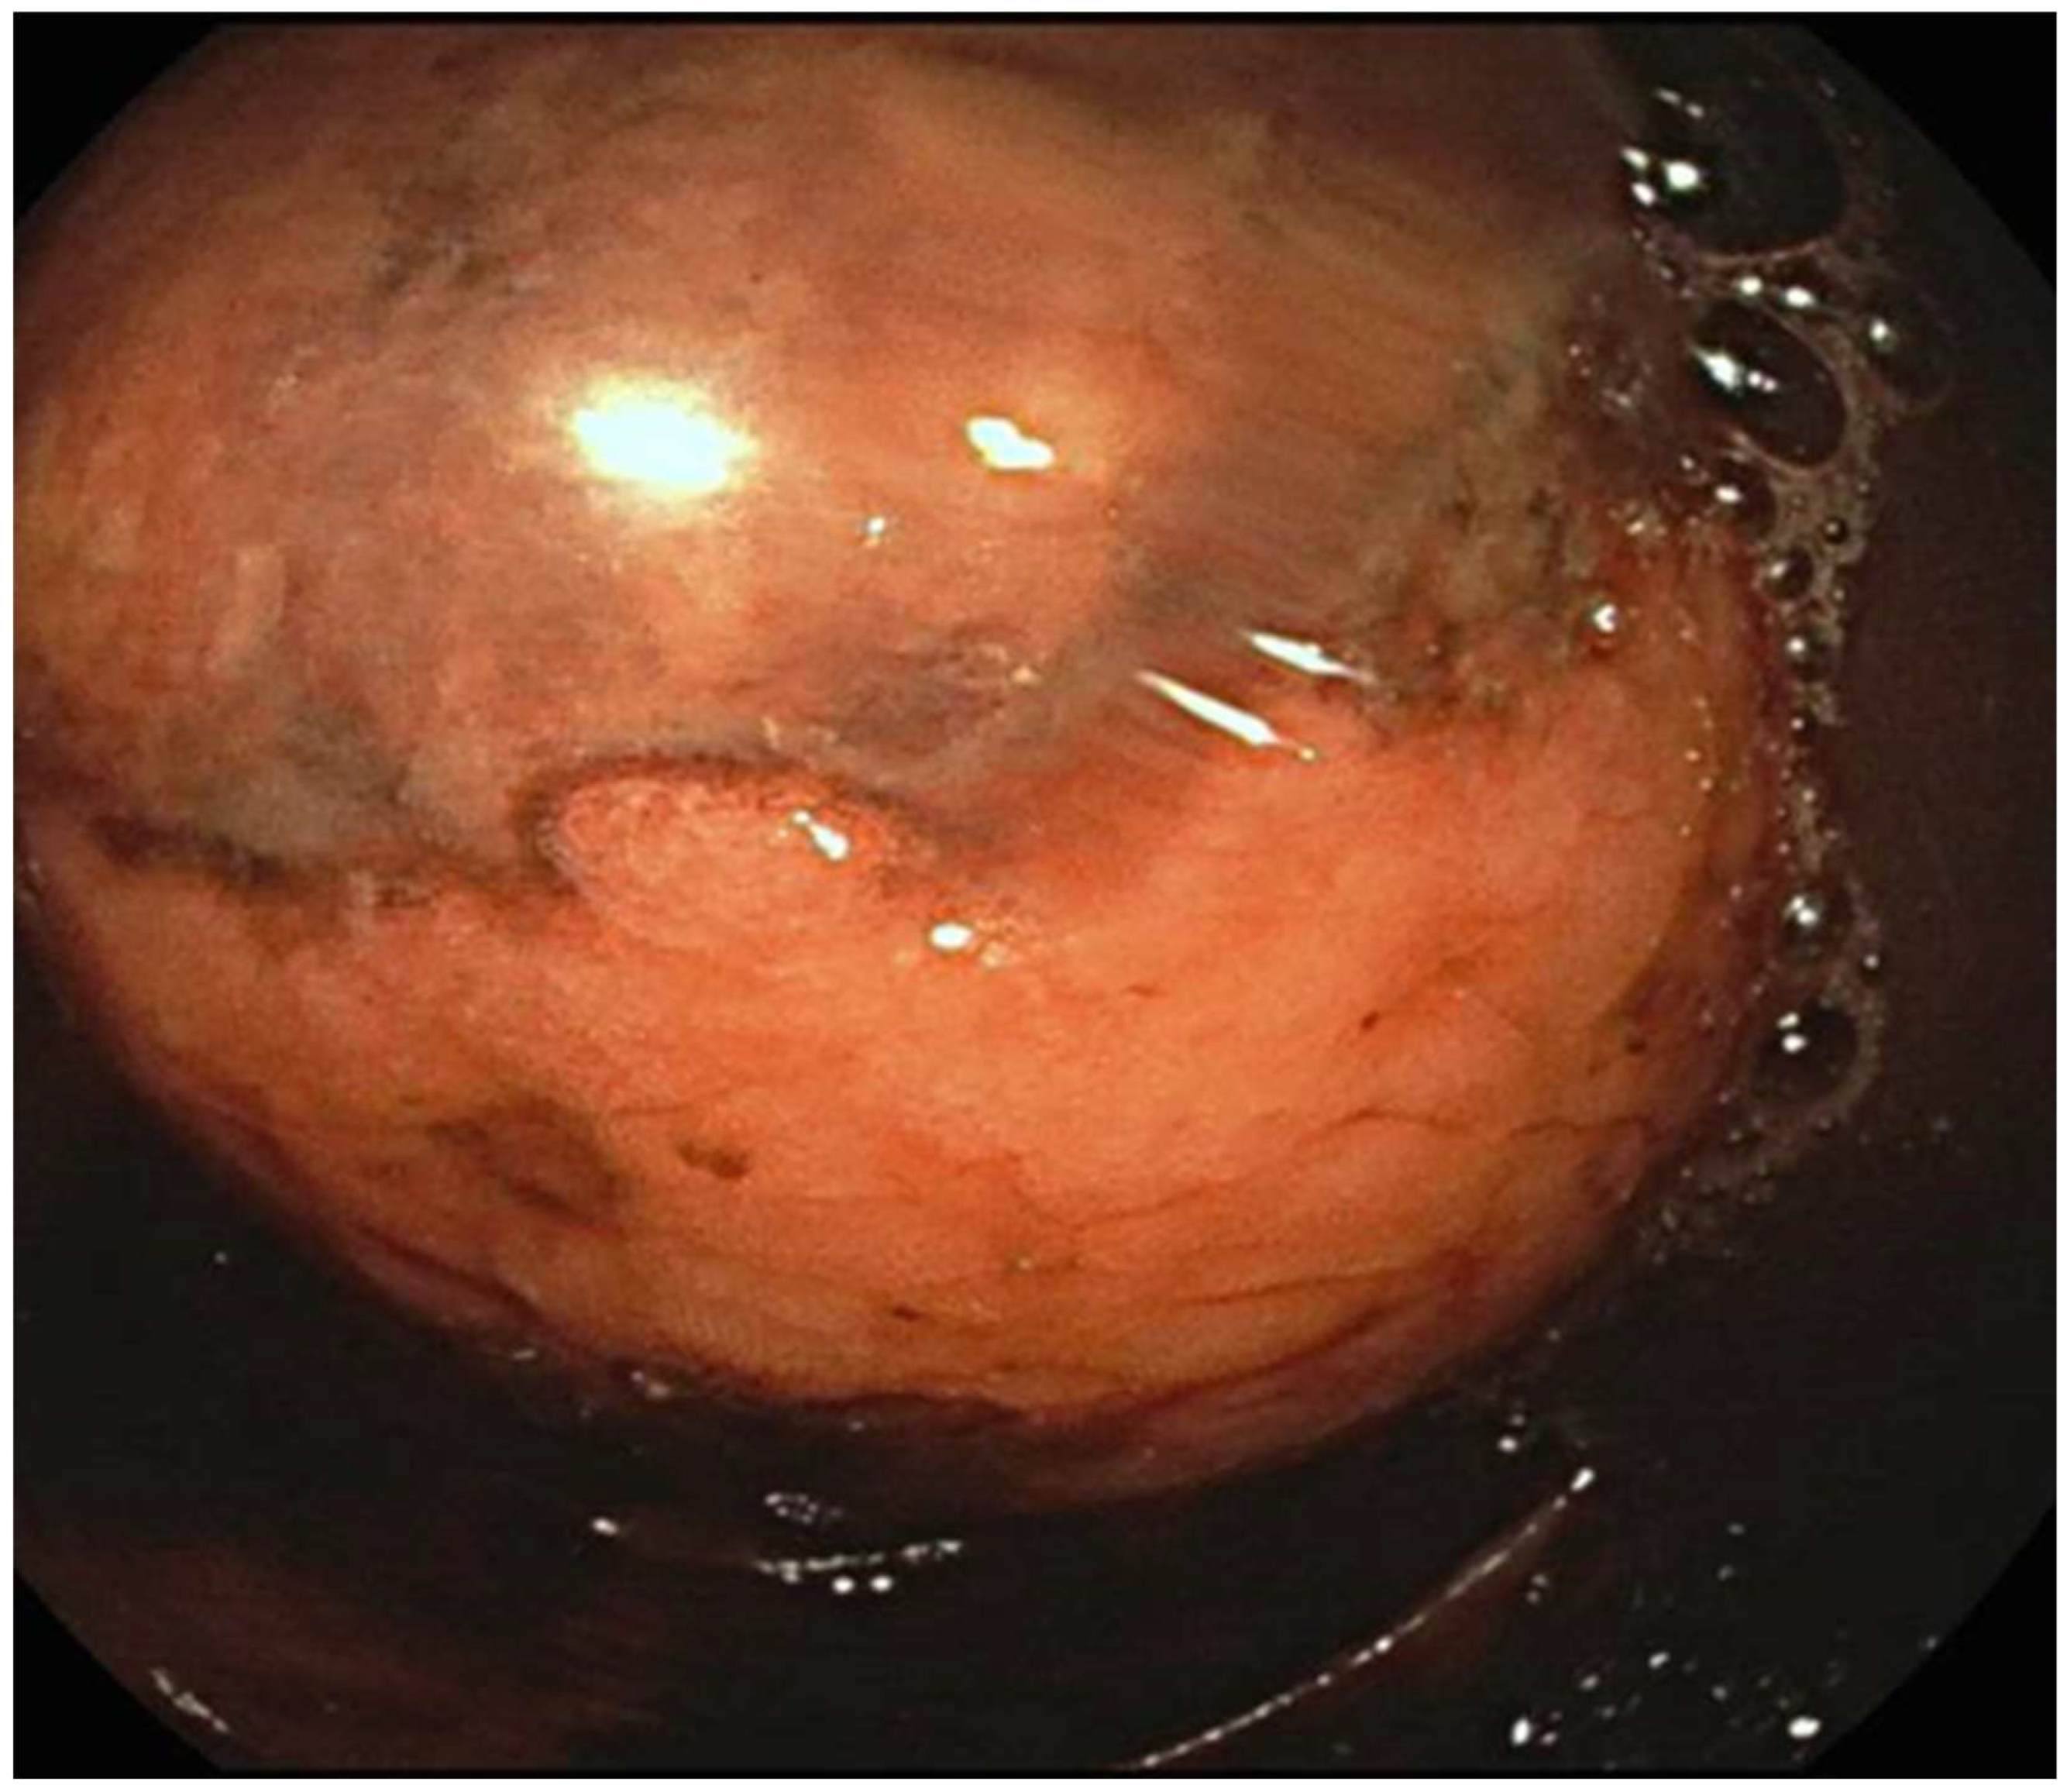

- 7 cases in which the lipoma was presumably associated with symptoms including abdominal pain, hematochezia, and even intussusception. In 3 of these cases, we had a pre-treatment diagnosis as the symptoms required the execution of pre-endoscopic radiological examinations.

- 8 cases in which the discovery and subsequent removal of the lipoma seem to be accidental, made during routine check-ups or follow-ups (obviously without warning symptoms).